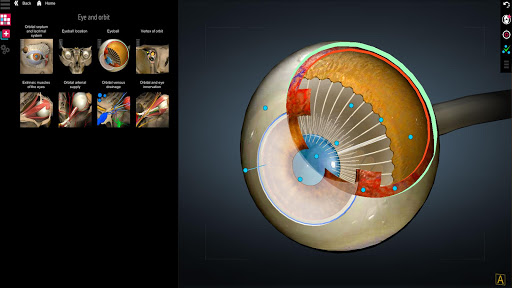

A true and totally 3D app for studying human anatomy, built on an advanced interactive 3D touch interface.

★ Sense organs